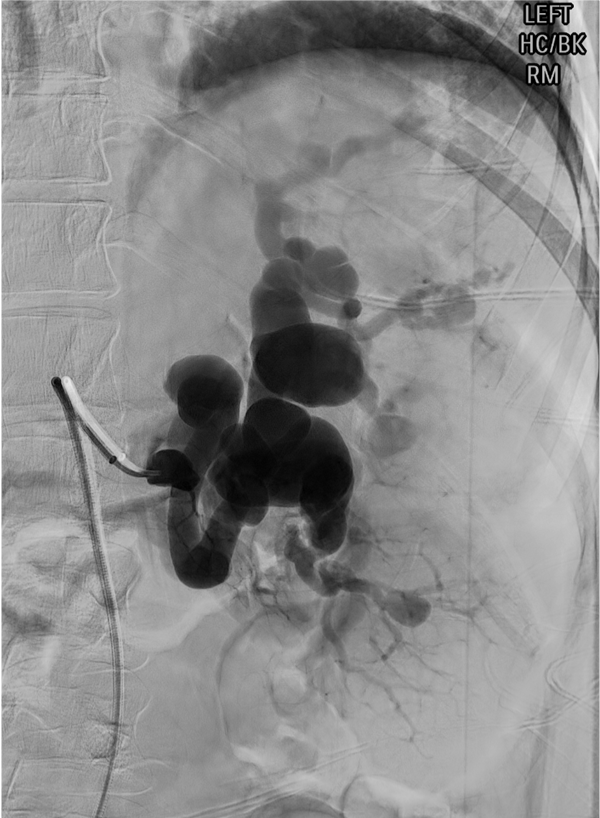

Splenic artery aneurysm — saccular dilation of the splenic artery trunk amenable to coil sandwich or covered stent exclusion.

Aneurysm indications: any splenic artery pseudoaneurysm; true aneurysm >2 cm, enlarging, symptomatic, in women of childbearing age, or pre-liver transplant.

Embolic selection: coils and vascular plugs for proximal and aneurysm embolization; microcoils, Gelfoam slurry, or particles for distal/selective; covered stents for select wide-neck aneurysms with preservation of splenic flow.